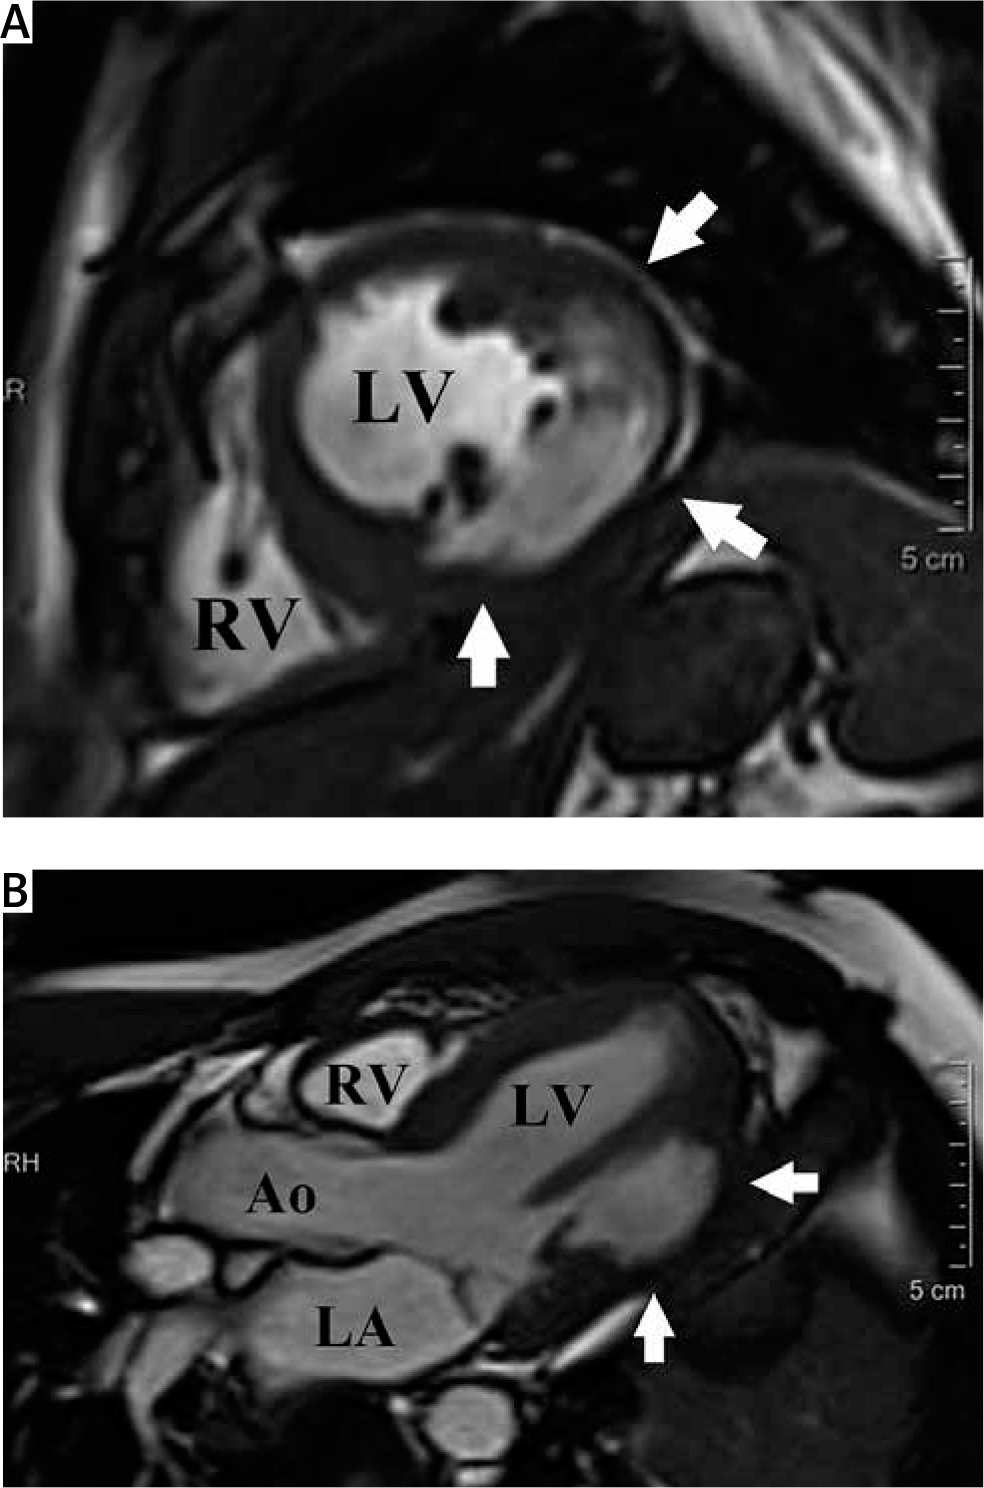

Cardiac magnetic resonance: short-axis view at the papillary muscle level (A) and 3-chamber view (B) demonstrating an incomplete wall rupture encompassing mid inferior, inferolateral and lateral segments of the left ventricle (arrows) Ao – aorta, LA – left atrium, LV – left ventricle, RV – right ventricle.

A 35-year-old man with no significant past medical history was admitted to the cardiology department with inferolateral ST-elevation myocardial infarction. Coronary angiogram performed immediately after admission (approximately 11–12 hours after the onset of chest pain) revealed right coronary artery occlusion, which was successfully revascularized by percutaneous coronary intervention (PCI) with drug-eluting stent implantation. Postprocedural transthoracic echocardiography showed left ventricular (LV) function abnormalities with ejection fraction reduced to 38%, akinesis of inferior, inferolateral and lateral segments, as well as an aneurysmatic bulge in the inferolateral wall, with wall thickness decreased to 3–4 mm. No pericardial effusion or evidence of cardiac tamponade were found. In view of these findings, urgent cardiac magnetic resonance (CMR) imaging was performed to further explore the morphology of LV wall thinning. This examination revealed incomplete free wall rupture (FWR) encompassing mid inferior, inferolateral and lateral segments (Figures 1 A, B).